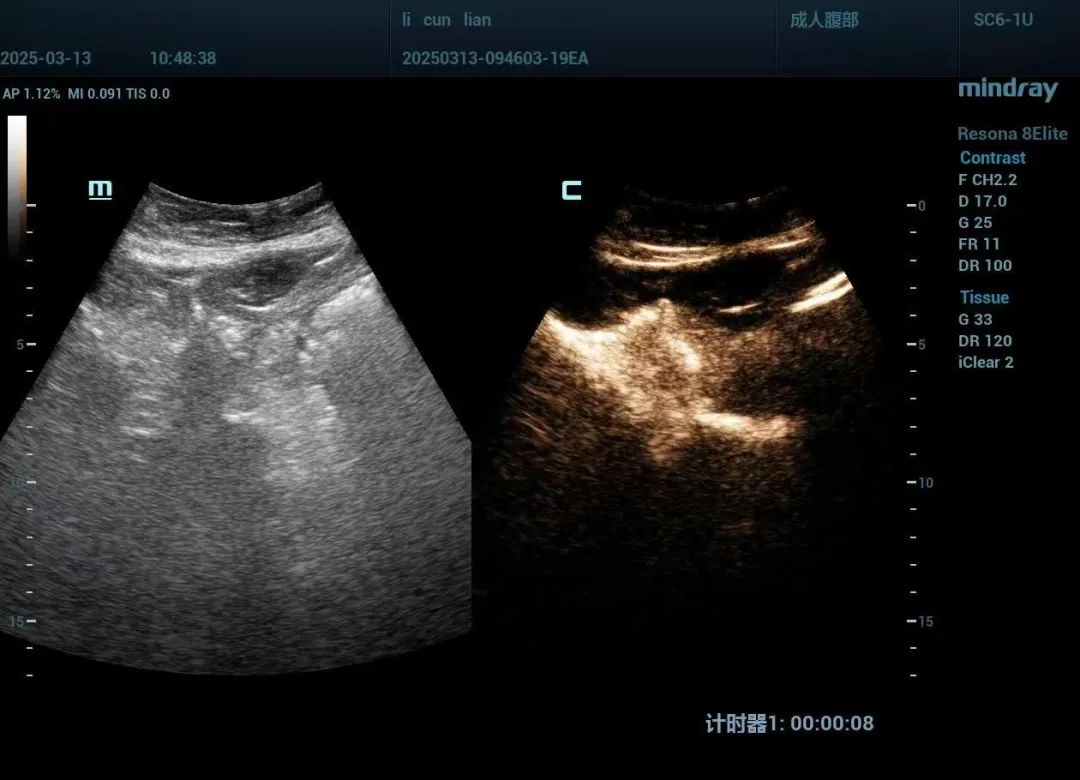

手术过程中,超声科团队在超声的精准引导下,将穿刺针准确置入肝左叶囊肿内,成功抽出约800ml黄色清亮液体,并注入稀释后的造影剂进行囊内造影。确认造影剂未进入肝内胆管及腹腔后,团队使用无水乙醇冲洗囊液至清亮,并注入了聚桂醇泡沫剂。整个手术过程顺利,李女士未出现任何不适反应,术后其右上腹症状完全消失。